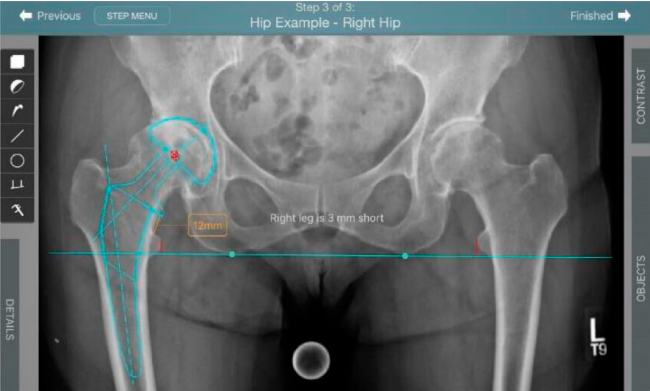

Planeación preoperatoria mediante la creación de plantillas digitales para reemplazo de cadera y análisis intraoperatorio

Mayor nivel de información intraoperatoria facilita la colocación correcta de los implantes:

Inclinación y anteversión de la copa acetabular para una correcta colocación del implante.

Verificación de la posición deseada del implante que potencialmente puede ayudar a reducir la probabilidad de dislocación protésica y aumentar la estabilidad de la articulación.

Anotaciones digitales y herramientas de análisis de longitud de pierna.